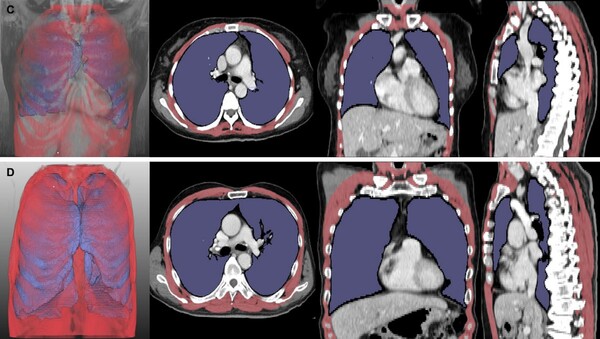

이에 연구팀은 서울대병원에서 진료받은 루게릭병 환자 261명의 흉부 CT 영상을 분석하고, 폐 용적 지수(LVI)와 호흡근 용적 지수(RMI)를 산출해 이 지수가 환자의 병기 및 생존 기간과 어떤 상관관계가 있는지를 평가했다. 연구 결과, LVI와 RMI는 병기가 진행될수록 유의하게 감소했으며, 두 지수가 낮은 환자는 높은 환자에 비해 기관절개술이나 사망에 이르는 시점이 더 빨랐다. 특히 구음장애가 동반된 환자에서도 LVI와 RMI가 독립적인 예후 지표로 작용하는 것이 확인됐다.

논문의 교신저자인 최규성 교수는 “이번 연구는 대규모 환자 데이터를 기반으로 딥러닝 기술을 활용해 루게릭병의 예후를 예측할 수 있는 정량적 영상 지표의 가능성을 최초로 입증했다”고 밝혔다. 공동저자인 최석진 교수는 “영상 기반 지표는 특히 기존 검사가 어려운 환자에서 임상 결정을 보조하는 데 큰 역할을 할 것으로 기대된다”고 전했다.